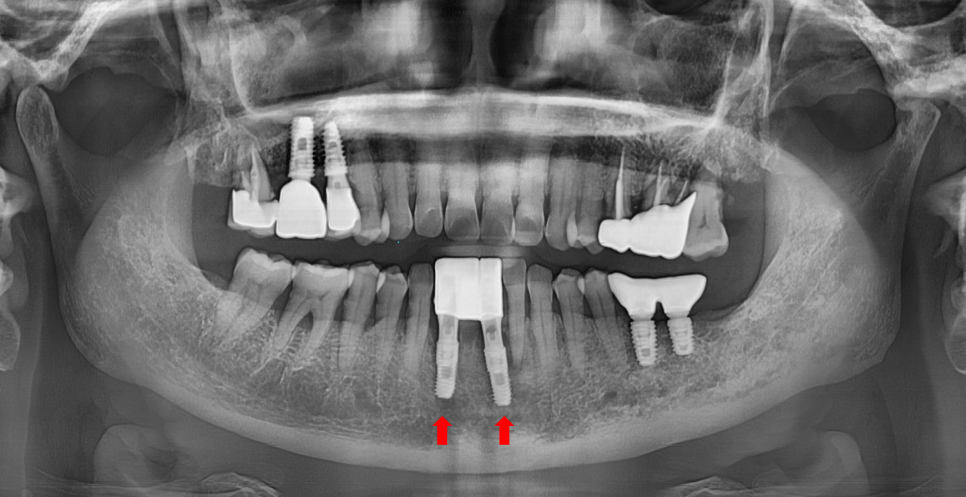

이 환자분도 결국 발치 후 임플란트를 권유드렸습니다.

240622

하악 전치부

그러니까 아래 앞니는 잇몸뼈가 얇아

작은 염증에도 뼈 소실이 빠르게 진행됩니다.

이런 해부학적인 특징 때문에 임플란트 역시

고난이도가 요구됩니다.

240711